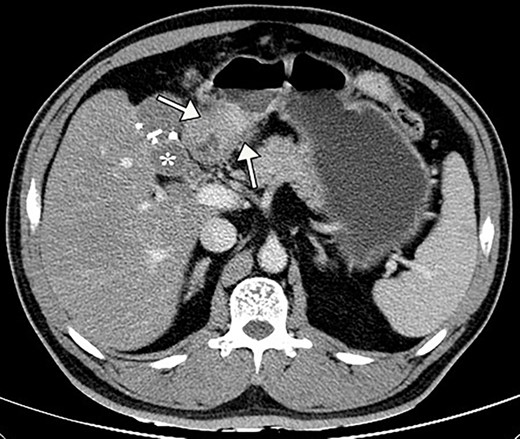

A 50-year-old Chinese man presented with right upper abdominal discomfort for 18 days. A computed tomography (CT) enhanced scan showed the thickened wall of the antrum and a cystic foci in the gallbladder bed (Fig. 1). Endoscopy revealed submucosal tumor with ulcer formation situated at the gastric antrum (Fig. 2). Pathology was positive for adenocarcinoma. His past history included hypertension, type 2 diabetes, hyperuricemia and hyperlipidemia. He had a medical history of laparoscopic cholecystectomy, performed 20 years ago for acute gangrenous cholecystitis. Physical examination revealed mild right upper epigastric tenderness.

Preoperative contrast abdominal CT scan showed the thickening antral wall with uneven enhancement (white arrows) and a cystic foci (white asterisk) in the gallbladder bed with hyperdense clips from previous cholecystectomy.